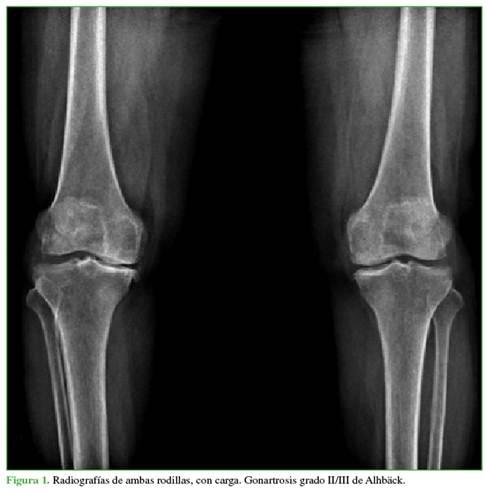

Caso de gonartrosis sintomática

Paciente 68 años de edad. Cirujano. Enfermedad articular degenerativa. Genu varo sintomático (Figura 1). Recientemente debió aumentar la dosis de la medicación analgésica y reducir la marcha.